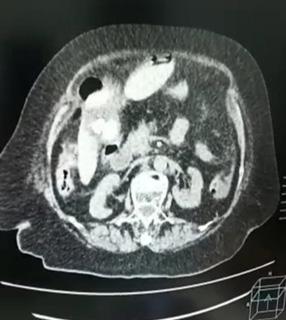

E. La exposición de un paciente es importante debido a las lesiones que se podrían omitir al estar en áreas no visibles. Posteriormente, es necesario el calentamiento del paciente, ya que la hipotermia puede contribuir a la aparición de complicaciones sistémicas, como las coagulopatías (10). No se debe olvidar la importancia de los estudios complementarios, como la radiografía portátil, la ecografiaFAST, que presenta una mayor sensibilidad para detectar neumotórax en comparación con la radiografía; 48,8 % vs 20,9 % (11). Además, la tomografía computarizada, electrocardiograma y laboratorios como el lactato sérico y el déficit de bases en la gasometría que se correlacionan con la mortalidad (12). Después de la evaluación primaria, se determinará si el paciente requiere una intervención quirúrgica de emergencia o se procederá a la evaluación secundaria, que consiste en una revisión detallada por sistemas y el uso de exámenes complementarios si es necesario. Con esta pequeña lectura creemos que se pueden realizar mas estudios locales para reflejar la importancia de la misma y preparar a mas estudiantes o profesionales en la atención de pacientes críticos.